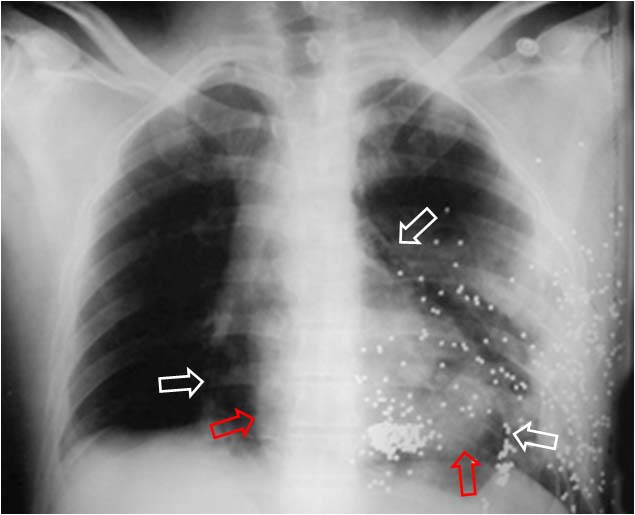

Signo de neumopericardio a tensión en la radiografía posteroanterior o anteroposterior de tórax. El neumopericardio es un hallazgo infrecuente que puede ocurrir en pacientes con traumatismo torácico. El signo del corazón pequeño consiste en una disminución del tamaño de la silueta cardiaca (como consecuencia del aumento de presión en el espacio pericárdico) y se acompaña de signos hemodinámicos de taponamiento cardíaco.

En la imagen, un caso de neumopericardio en un cadáver. Las radiodensidades puntiformes del hemitórax izquierdo corresponde a múltiples perdigones . Las flechas blancas marcan el contorno pericárdico y las rojas el cardiaco. Entre ambas, la zona radiolucente corresponde al neumopericardio.